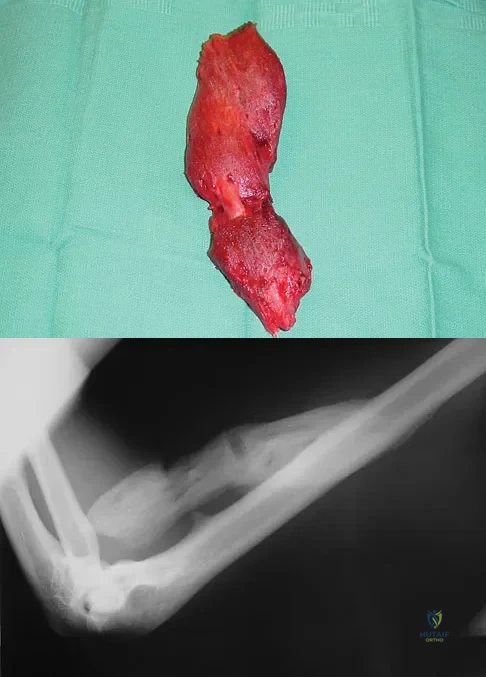

A 30-year-old man has had intermittent swelling of his right ankle for the past 6 months. He denies any history of trauma. Radiographs reveal osteolytic changes on both sides of the joint. An axial CT scan and a T2-weighted MRI scan are shown in Figures 40a and 40b. He undergoes surgical excision. An intraoperative photograph and a biopsy specimen are shown in Figures 40c and 40d. What is the most likely diagnosis?

Explanation